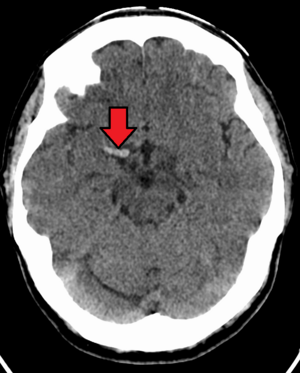

Cerebral venous sinus thrombosis

Cerebral venous sinus thrombosis (CVST) is a rare form of stroke which results from the blockage of the dural venous sinuses by a thrombus. Symptoms may include headache, abnormal vision, any of the symptoms of stroke such as weakness of the face and limbs on one side of the body and seizures. The diagnosis is usually made with a CT or MRI scan. The majority of persons affected make a full recovery. The mortality rate is 4.3%.[9]